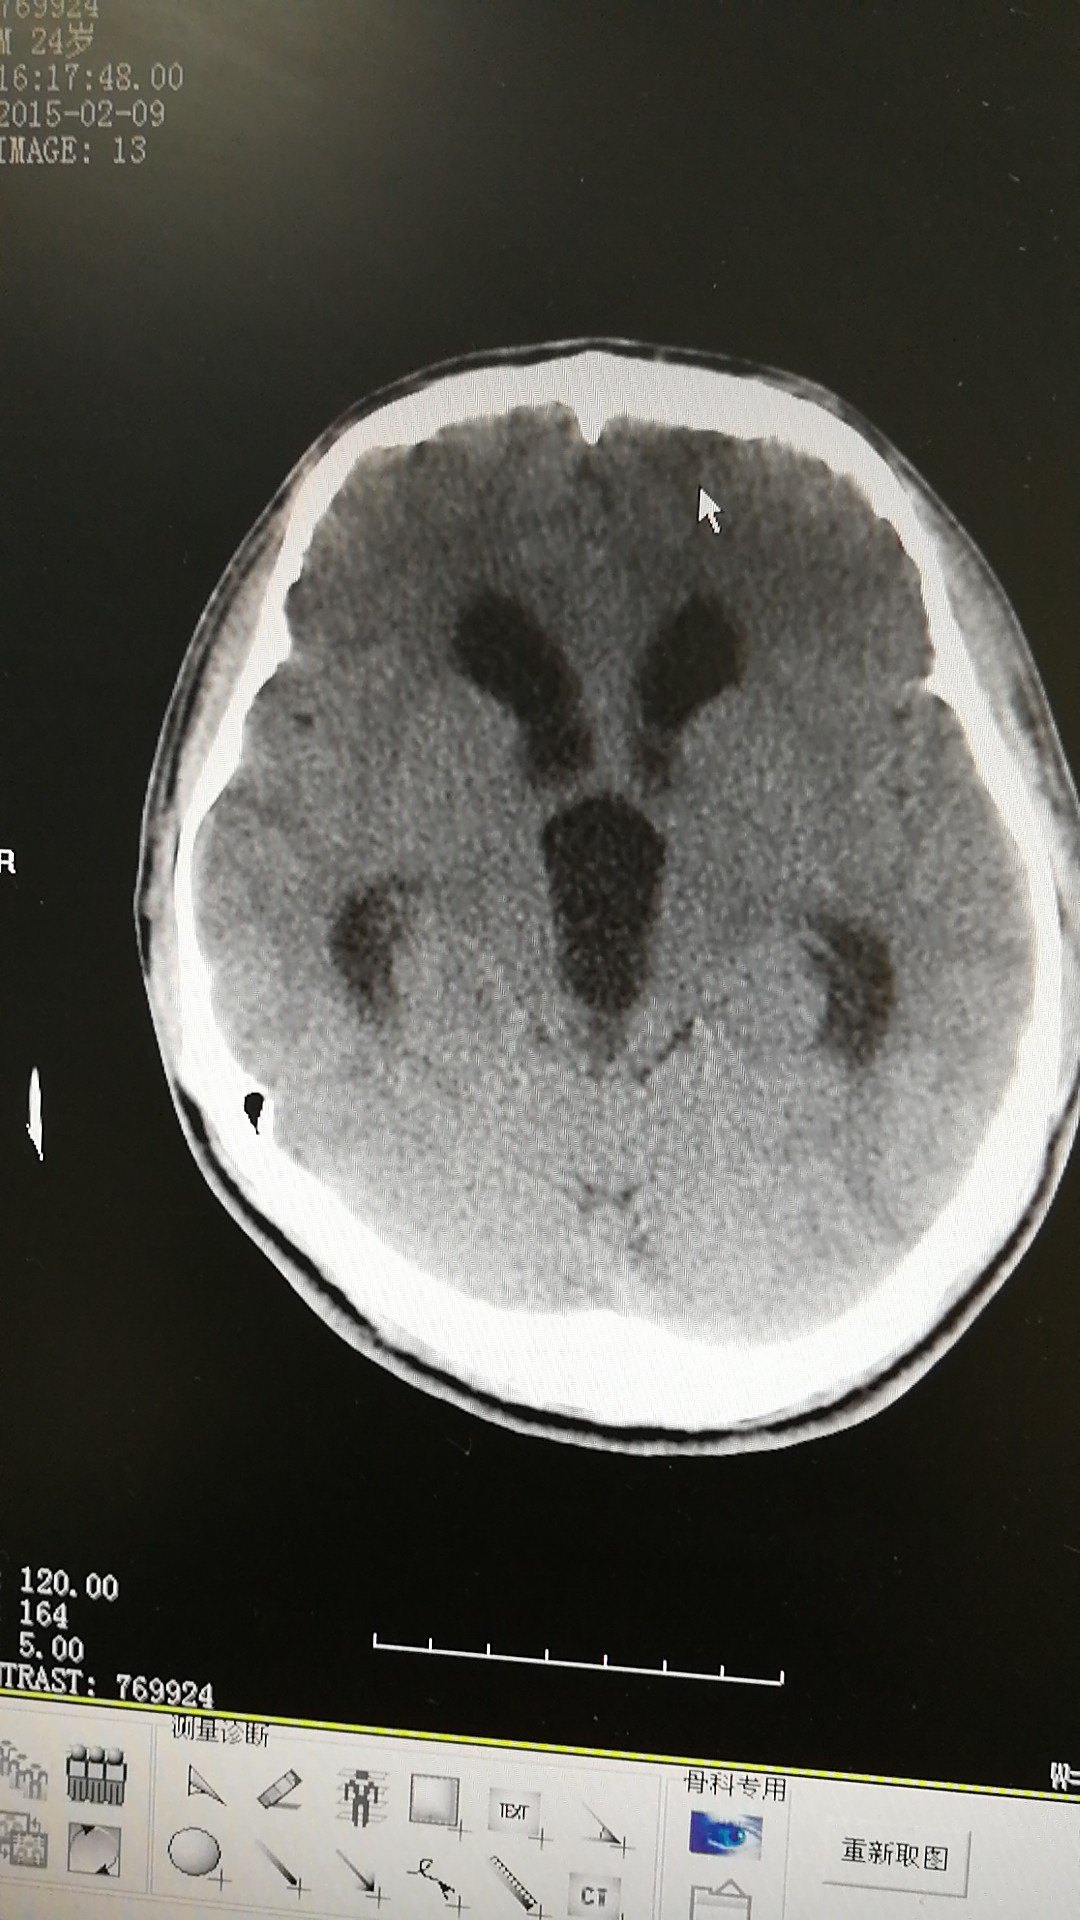

脑积水ct显示:侧脑室,三脑室扩大有症状的脑积水应该及时手术治疗.

脑积水ct影像